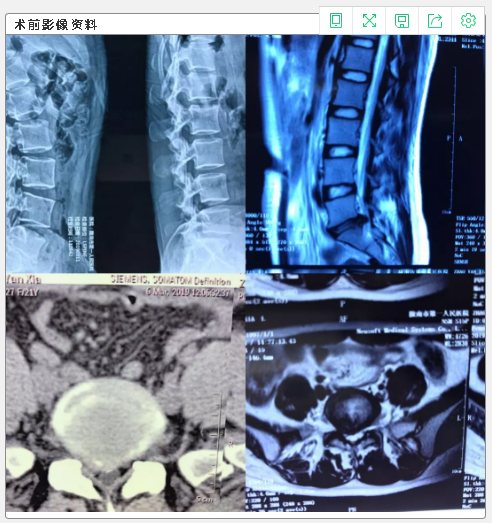

我院骨一科成功实施两例腰椎间盘突出椎间孔镜下髓核摘除术

3月19日中午,我院骨一科特邀甘肃省人民医院脊柱外科刘林主任指导,在局麻下成功实施两例腰椎间盘突出椎间孔镜下髓核摘除术,为两位腰椎间盘突出的患者解除病痛,手术效果良好,这是我院骨科开展的又一脊柱外科微创新技术。

患者王某,女,27岁,腰疼痛伴左下肢麻木一年加重三天。入院查体:腰4、5棘突及椎旁轻压痛,叩击痛,按压左侧椎旁伴左下肢放射痛,直腿抬高试验45度,加强试验阳性,左小腿外侧及左足外侧麻木。

患者赵某,女,21岁,腰部疼痛1年余加重伴右下肢麻木1月。查体:腰5棘突及椎旁轻压痛,叩击痛,右下肢直腿抬高实验约40度,加强实验阳性,右足跟及足外侧缘麻木,下肢肌力未见异常。

随着微创技术的发展,目前通道显微镜下椎间盘摘除手术、经皮椎间孔镜椎间盘摘除手术已成为椎间盘突出症的主要治疗技术,具有手术创伤小、患者痛苦少、恢复快、住院时间短、费用相对较低等优点。而传统手术创伤大、手术视野较小、术后恢复时间长。该手术的成功开展,取得了良好效果,标志着我院骨科脊柱微创技术再上新台阶。